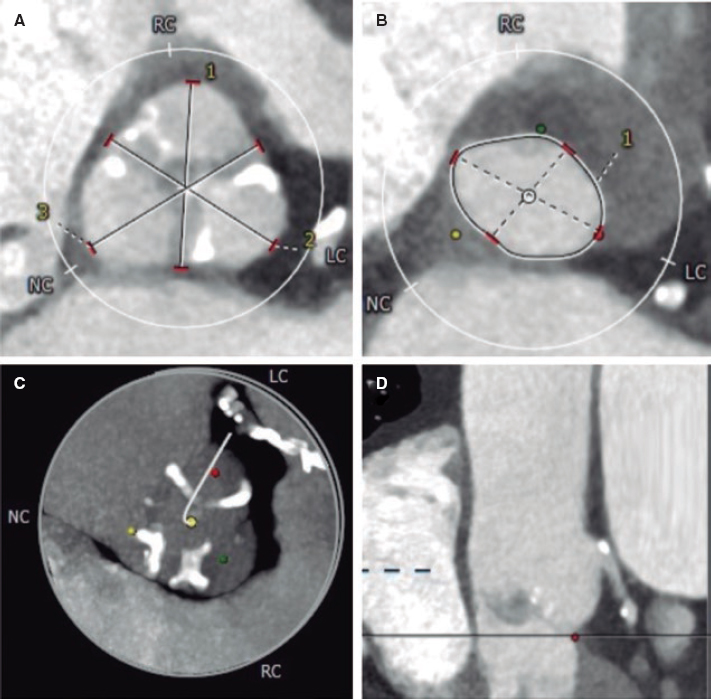

The quantitative analysis of leaflets and annulus is performed through multiplanar reconstructions of 3D views.13 By placing orthogonal views on the tricuspid annulus at the leaflet insertion site, the TV short axis is acquired. After precise adjustment the annular diameters and area dimensions can be obtained (figure 1 of the supplementary data).

The prosthesis is available in 5 different sizes (36 mm, 40 mm, 44 mm, 48 mm, and 52 mm). A slight oversizing (from 5% to 10%) with respect to the annular dimensions is advisable. To select the device size, it is required to measure the annulus using TEE and computed tomography scan. On the CAT scan, the distance between the annulus to the right coronary artery is a very important feature to avoid damage and have guidance during the procedure. The x-ray projection imaging of the implant is also derived from the CAT scan.